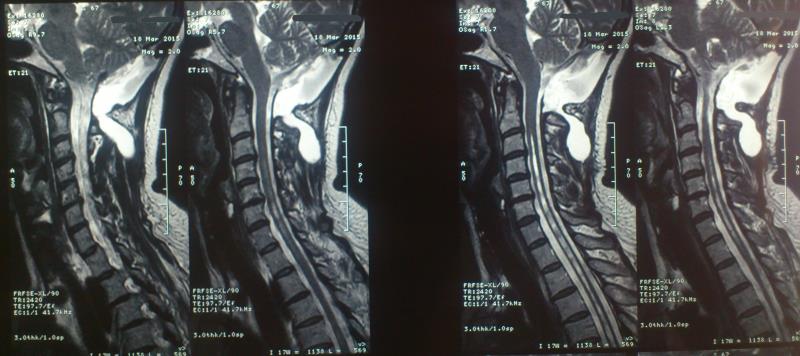

Ασθενής  γυναίκα 49 ετών προσήλθε λόγω υπινιακής κεφαλαλγίας εκλυόμενης και επιδεινούμενης  κατά την επίκυψη και  την άρση βάρους  ( Valsalva maneuvers ) με συνοδό αίσθημα αιμωδιών  άνω και κάτω άκρων. Ο προεγχειρητικός έλεγχος με μαγνητική τομογραφία  του κρανιοσπονδυλικού άξονα ανέδειξε εικόνα συμβατή με Chiari τύπου I : κατάσπαση των παρεγκεφαλιδικών αμυγδαλών 8 mm με κατάληψη- συμφόρηση του ινιακού τρήματος και συνοδό συριγγομυελία καθ’ όλο το μήκος του αυχενοθωρακικου μυελού. Η ασθενής υποβλήθηκε σε υπινιακή κρανιοτομία, αφαίρεση του οπίσθιου τόξου του άτλαντα (Α1) και εκτομή των παρεγκεφαλιδικών αμυγδαλών αποκαθιστώντας την υδροδυναμική του εγκεφαλονωτιαίου υγρού. Πραγματοποιήθηκε πλαστική σκληράς μήνιγγος και δεν επανατοποθετήθηκε ο οστικός κρημνός. Η ασθενής μετεγχειρητικά παρουσίασε  πλήρη ύφεση της κεφαλαλγίας και σταδιακή αποκατάσταση των αιμωδιών. Ο μετεγχειρητικός απεικονιστικός έλεγχος ανέδειξε την αποσυμπίεση στο επίπεδο της κρανιοσπονδυλικής συμβολής και σαφή μείωση των διαστάσεων της συριγγομυελίας.

Προεγχειρητικός απεικονιστικός έλεγχος